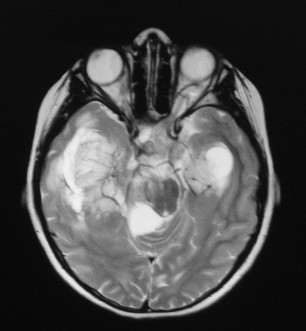

Scientists using an extract of whole-plant marijuana rich in pot’s main psychoactive ingredient THC as well as cannabidiol (CBD) showed “dramatic reductions in tumor volumes” of a type of brain cancer.

“High-grade glioma is one of the most aggressive cancers in adult humans and long-term survival rates are very low as standard treatments for glioma remain largely unsuccessful,” according to researchers Katherine A. Scott, Angus G. Dalgleish, and Wai M. Liu from the Oncology Department at St. George’s University of London.

Tumors treated this way in mouse models for glioma showed “dramatic” results, with pot-treated tumors shrinking to nearly one-tenth the size of tumors in the control group.